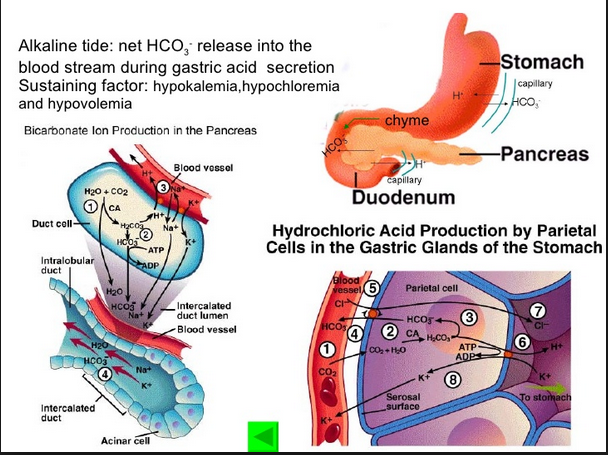

Digestive Discussion orders per HCL agent Hillary CL

Role of Hydrochloric Acid in the Stomach | LIVESTRONG.COM

Apr 11, 2011 – Hydrochloric acid, also called HCl, is a clear, highly corrosive liquid. HCl is one of the many chemicals released in our stomach when we eat a …

HCl tenure as Secret of ate … food for thought mystery